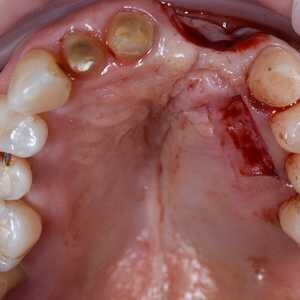

Dans cet article, nous présentons un cas clinique qui montre comment une mauvaise mise en place d'un implant peut rendre impossible la réhabilitation prothétique, ce qui nécessite une nouvelle planification chirurgicale et de réhabilitation pour obtenir l'esthétique souhaitée. Le patient se présente à notre observation avec une réhabilitation prothétique incongrue, avec bride en résine, support dentaire et implantaire, avec la présence d'un implant en position 2.1 vestibulaire et avec l'émergence dans le fornix, dans la mucosa alvéolaire. L'évaluation de la tomodensitométrie montre la position incorrecte de l'implant et la perte constante dans le sens transversal de la structure osseuse (Figs. 1, 2). Par conséquent, le plan de traitement suivant a été choisi : retrait de l'implant et préparation prothétique de l'élément 2.3, fabrication d'un premier support dentaire temporaire pour guider la cicatrisation des tissus (Figs. 3-7). Après 4 mois, une greffe d'épithélium conjonctif libre est réalisée avec ablation du palais pour compenser l'espace transversal des tissus mous, puis le provisoire est remodelé afin de faciliter la cicatrisation des tissus (Figures 8-11). Après 9 mois de maturation des tissus, la finalisation prothétique fixe avec support dentaire est réalisée (Figs. 12-14).